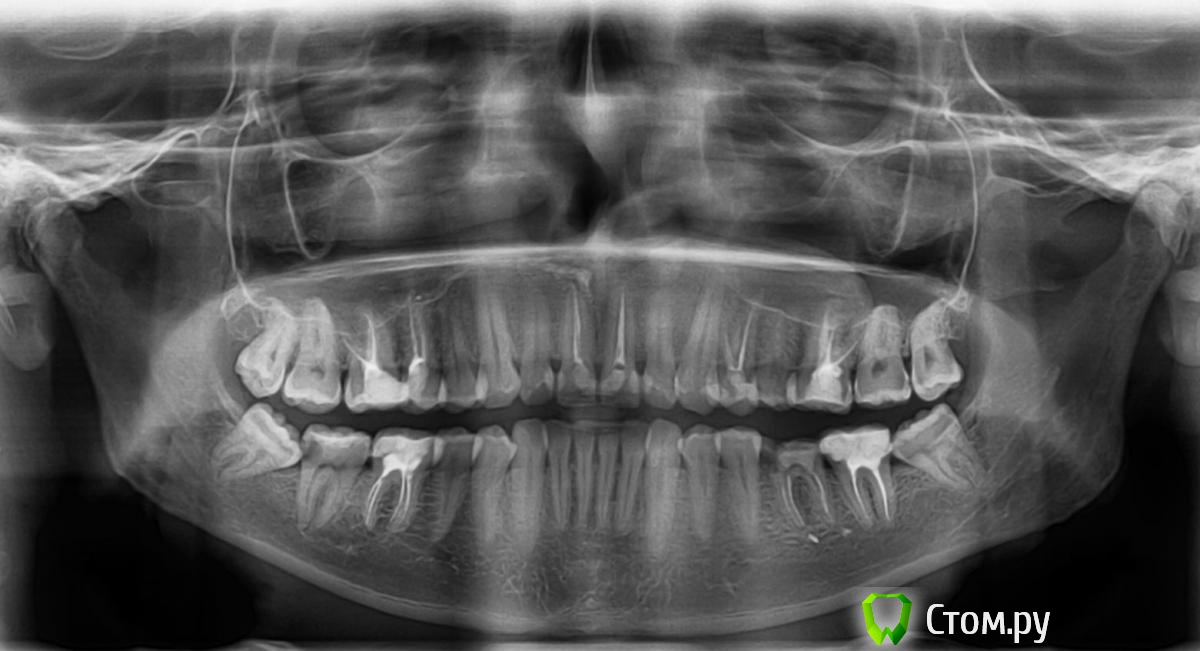

Closius Опубликовано 28 июня, 2014 Автор Поделиться Опубликовано 28 июня, 2014 Для начала почитайте правила форума http://forum.stom.ru/topic/2813-obiazatelno-k-prochteniiu/Теперь по вопросам1. Выбирать нужно не Импланты, а врача2. Сможете, если кроме акробатики и велосипеда, займетесь силовыми видами - ортопед изготовит защитную каппу3. Дооолго, может и всю жизнь4. Сейчас администраторы удалят, попробуйте поискать врача здесь http://forum.stom.ru/topic/16116-posovetuite-khirurgaimplantologa/Для новых вопросов выкладывайте снимки Прошу прощения... Спасибо за отклик! Прикрепил снимок. Может можно ее что-то сказать? Ссылка на комментарий

red_butler Опубликовано 28 июня, 2014 Поделиться Опубликовано 28 июня, 2014 1. Удалить все зубы мудрости2. Повторное лечение корневых каналов 1.6 1.1 2.4 2.6 и возможно 3.7 4.63. Лечение 4.7 - кариес из-за зуба мудрости4. Имплантация в позицию 3.6 через 3-4 месяца5. Протезирование 1.6 1.1 2.1 2.4 2.6 3.7 3.6 4.6 и возможно 4.7 6. Кт верхние челюстного синуса слева и консультация ЛОРа Ссылка на комментарий

red_butler Опубликовано 28 июня, 2014 Поделиться Опубликовано 28 июня, 2014 1. Расположены неправильно, создают ретенционные пункты для пищи, и как результат проблемы с соседними зубами2. Если не перелечите - хронические воспалительный процесс приведет к потере зубов, в корневых каналах остались микроорганизмы3. К сожалению, похоже что это уже не кариес, а пульпит. 4. Вспомните свой удаленный зуб, на ошибках нужно учиться5. По ОПГ заподозрил проблемы в левой гайморовой пазухе, кт - компьютерная томография Ссылка на комментарий